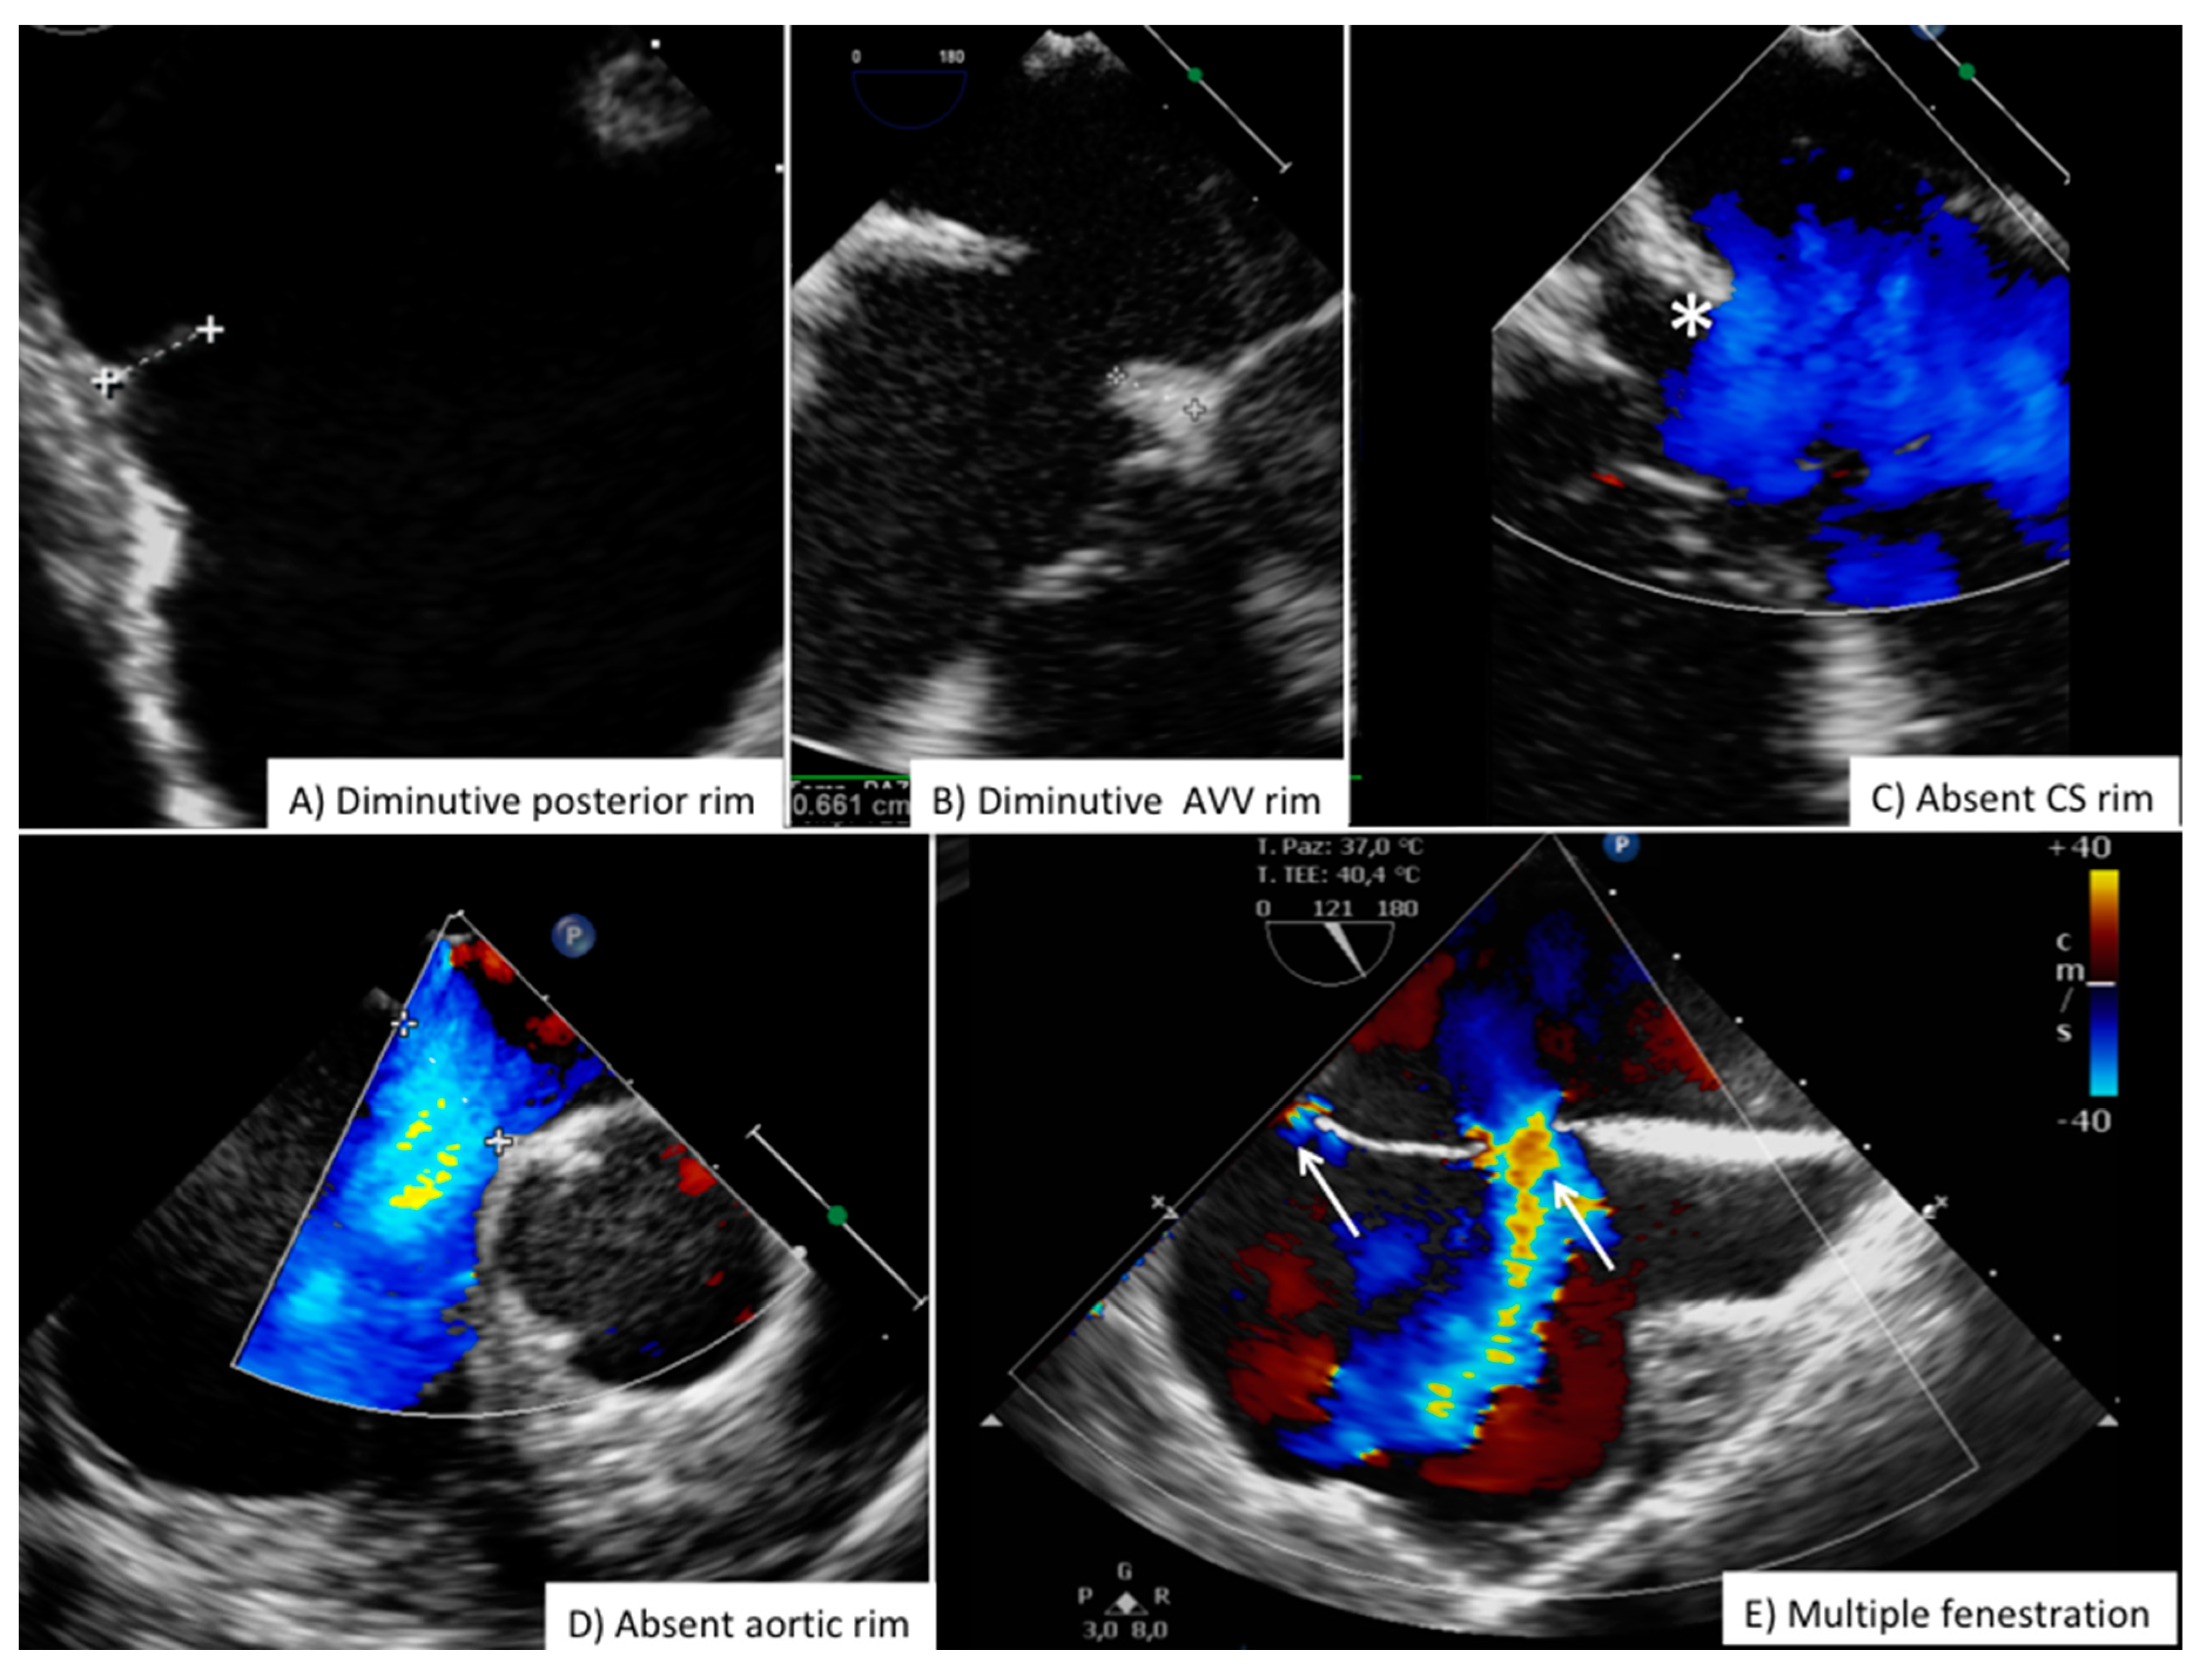

Although there are slight differences between children and adult patients, current indication for ASD closure requires large left-to-right shunt with evidence of right ventricular volume overload and normal pulmonary vascular resistance (Figure S1 Online Supplementary Material) [1,18,19]. Full right cardiac catheterization is usually not required in children and young adults, it may be necessary in older adults or in patients with specific risk factors for pulmonary vascular disease or restrictive left ventricular/atrial physiology [20]. The great majority of patients referred for ASD closure are evaluated with transthoracic echocardiography (Table 2). Pre-closure transesophageal echocardiography is often considered in adult patients with sub-optimal transthoracic windows or in cases with marginal anatomical suitability (Table 2). Figure 7 summarizes pre-ASD frequent high risk or suboptimal anatomical features (we do not recommend routine ASD closure in children less than 15 Kg of weight, and in children <30 Kg some restriction may apply depending on the relative ASD size compared to body surface area and surrounding structure) [21]. Pre-procedural measurement of the length of atrial septum in 4-chamber transthoracic view will help to ensure that the hypothetical left atrial disc (which can be up to 16mm larger than device waist) will fit.

Routine high risk anatomies include diminutive posterior and SVC rim (<5 mm), very large defect (>30 mm), thin and flimsy rim tissue; the absence of aortic rim is not considered an absolute contraindication but it has been associated to increased risk of erosion and embolization in particular if SVC border is also diminutive or absent (Figure 7) [23].

Figure 7. Challenging anatomies for ASD closure. Common anatomical features increasing procedural complexity and complication rate during ASD closure. ASD = secundum type Atrial Septal Defect; AVV = Atrio-Ventricular Valve; CS = Coronary Sinus.